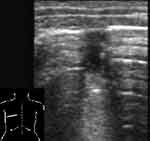

Плоская форма безвоздушного участка, когда в одном срезе он имеет размеры до нескольких см, а в перпендикулярной ему плоскости гораздо меньше, свидетельствует об ателектазе (Рис. 4, 5). При обширных безвоздушных участках на его присутствие указывает более острый конус безвоздушного сегмента, более высокое стояние края легкого, чем на противоположной стороне. В отличие от пневмонии в ателектазе не визуализируются эхогенные полоски содержащих воздух бронхов [7]. Исключение могут составлять крупные ателектазы у новорожденных, поскольку причина их возникновения не обструкция бронха, а нерасправление части легкого. Позади безвоздушных участков регистрируются усиленные эхосигналы.

[Увеличить]

Рис. 4. Небольшой ателектаз.

Рис. 5. То же, что на Рис. 4, во взаимно перпендикулярной плоскости.